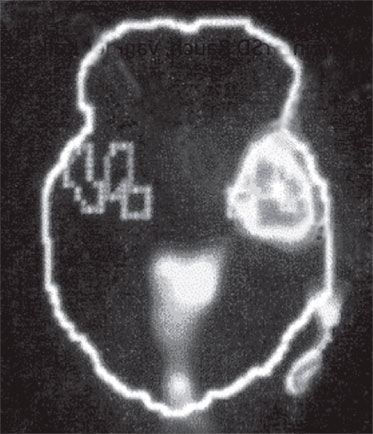

А. Правая лимбическая область

Б. Зрительная кора

В. Зона Брока

Изображение мозга в процессе переживания травмы. Светлые пятна в лимбической коре (А) и зрительной коре (Б) соответствуют повышенной активности мозга в этих участках. На снимке (В) видна значительно пониженная активность речевого центра мозга.

Когда через эту процедуру прошли все восемь участников, Скотт Рауч вместе со своими математиками и статистиками взялся за создание составного снимка, по которому можно было бы наглядно сравнить активность мозга в нейтральном состоянии и в момент появления неприятных воспоминаний. Несколько недель спустя он отправил мне результаты, которые вы видите выше. Я приклеил эти снимки на дверцу своего холодильника в кухне и на протяжении следующих нескольких месяцев каждый вечер их разглядывал. Должно быть, именно так чувствовали себя первые астрономы, взглянув через телескоп на неизученное звездное скопление.

На снимках были некоторые сбивающие с толку точки и цвета, однако самая яркая область активации мозга – большое красное пятно в правом нижнем центре мозга, известном как лимбическая область, или эмоциональный мозг, – никакого удивления не вызывала. Мы уже знали, что сильные эмоции активируют лимбическую систему, в особенности участок внутри нее, известный как миндалевидное тело.

Больше всего из полученных нами результатов нас поразила белая точка в левой фронтальной доле коры, так называемой зоне Брока. В данном случае изменение цвета означает значительный спад активности в этой области мозга.